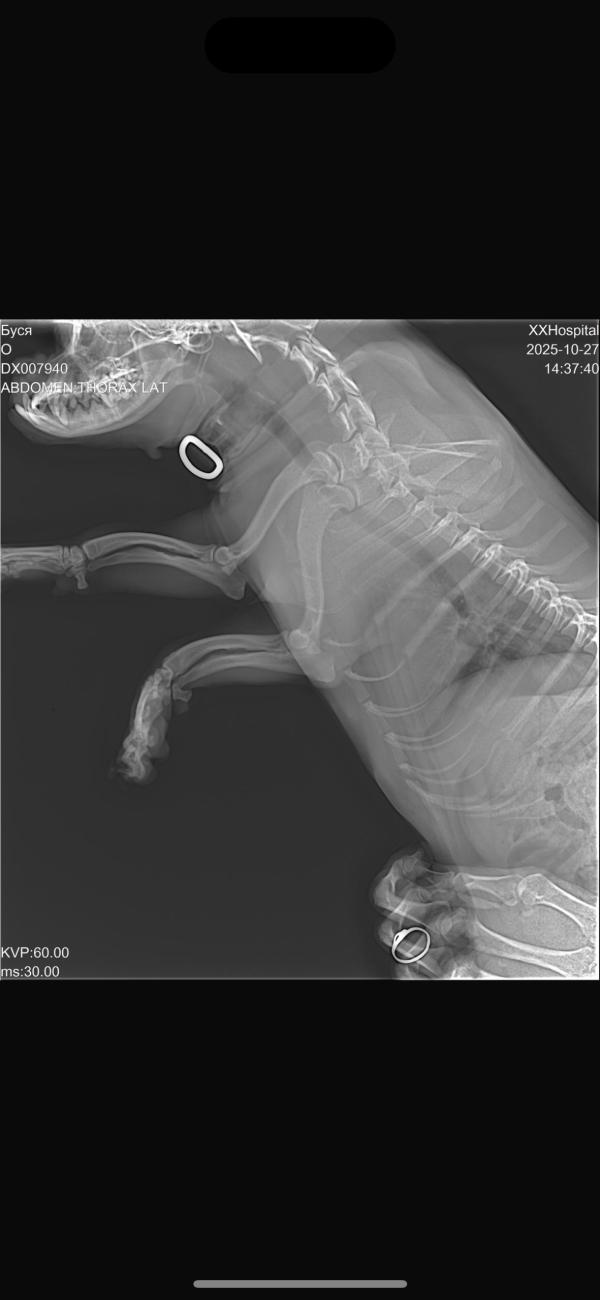

Собака осмотрена, сделан рентген во всех проекциях. Все цело - сильный ушиб и следить ! И в очередной раз я подумала как хорошо когда есть деньги и возможности. Будьте бдительны и если есть возможность всегда помогайте и оставайтесь людьми🫶

Повезло что вы были рядом. Вчера в клинике как раз были. Снимок 1000 за штуку, а надо несколько проекций. Ну и прием врача 3-4 тысячи.

1600 одна проекция 😏да ! Но пусть главное все здоровы деньги я заработаю это не такая проблема !

Вы молодец, но ... Надеюсь хозяева собаку покажут другому специалисту. У нее не все хорошо..

@ty_ktonastya вот на этих снимках лёгкие получше, чем на фото в посте. нужно быть начеку. Может ушиб, а может и отек быть. Предупредите хозяев